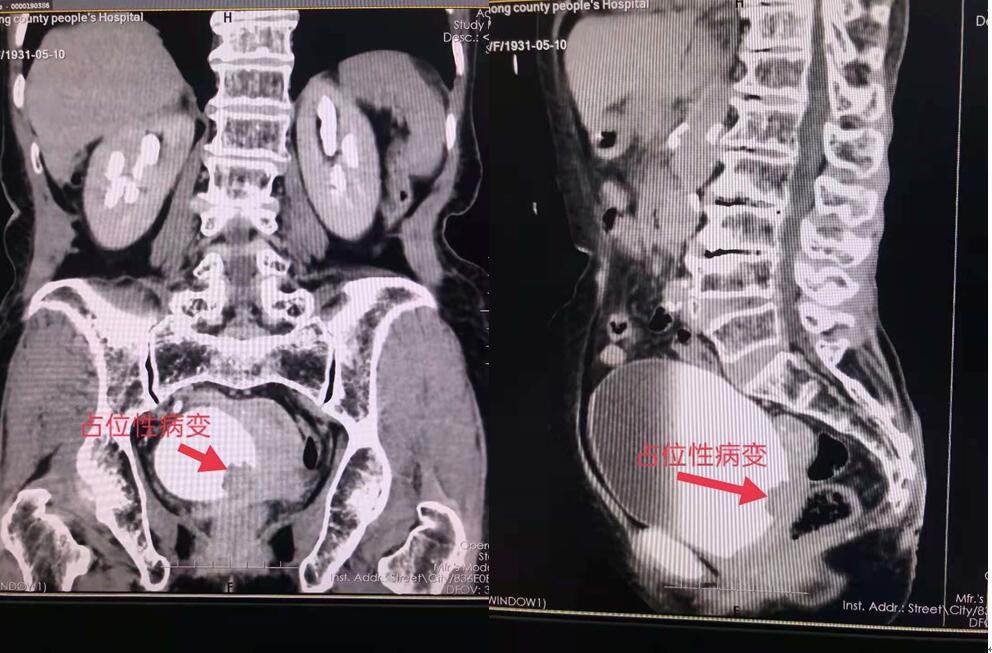

四、开展项目:科室现常规开展全身各部位CT平扫及增强检查、CT三维重建、CT血管造影(CTA、CTV)、(包括冠状动脉CTA)、CT尿路造影(CTU)、全身各部位DR摄片检查、床边摄片、同时开展胆系T管造影、CT定位下穿刺活检。

常规CT增强检查